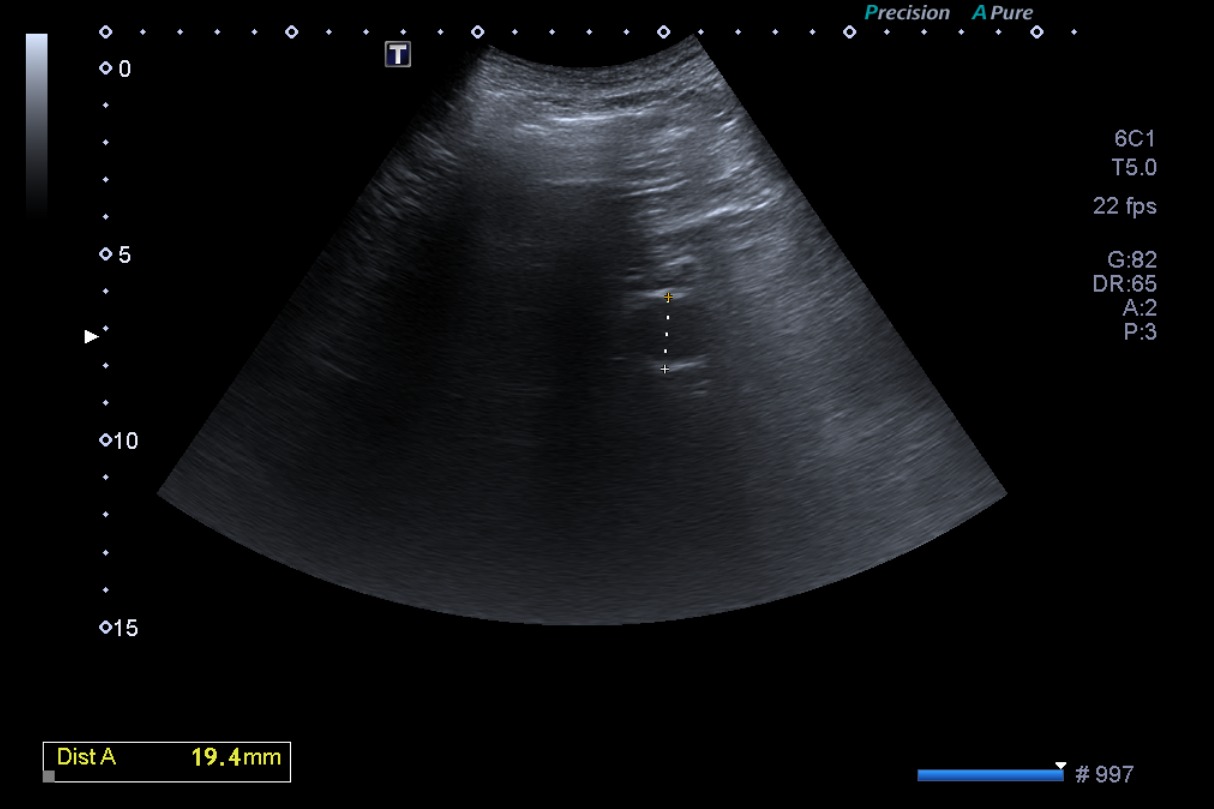

Consulta ahora por astenia, hiporexia, dudosa pérdida de peso, náuseas y vómitos no relacionados con la ingesta.

• Ecografía 2 (actual): lesión hiperecogénica en lóbulo hepático izquierdo, no visualizada en el estudio previo. Pared de vesícula biliar engrosada globalmente, 5 mm.

• Analítica sanguínea: discreta elevación de enzimas de colestasis y bilirrubina a expensas de la directa, velocidad de sedimentación globular 54 mm/hora.

En el contexto de la sintomatología del paciente, los antecedentes, y las características de la imagen hepática de nueva aparición en ecografía, se plantea el diagnóstico de una probable metástasis hepática.